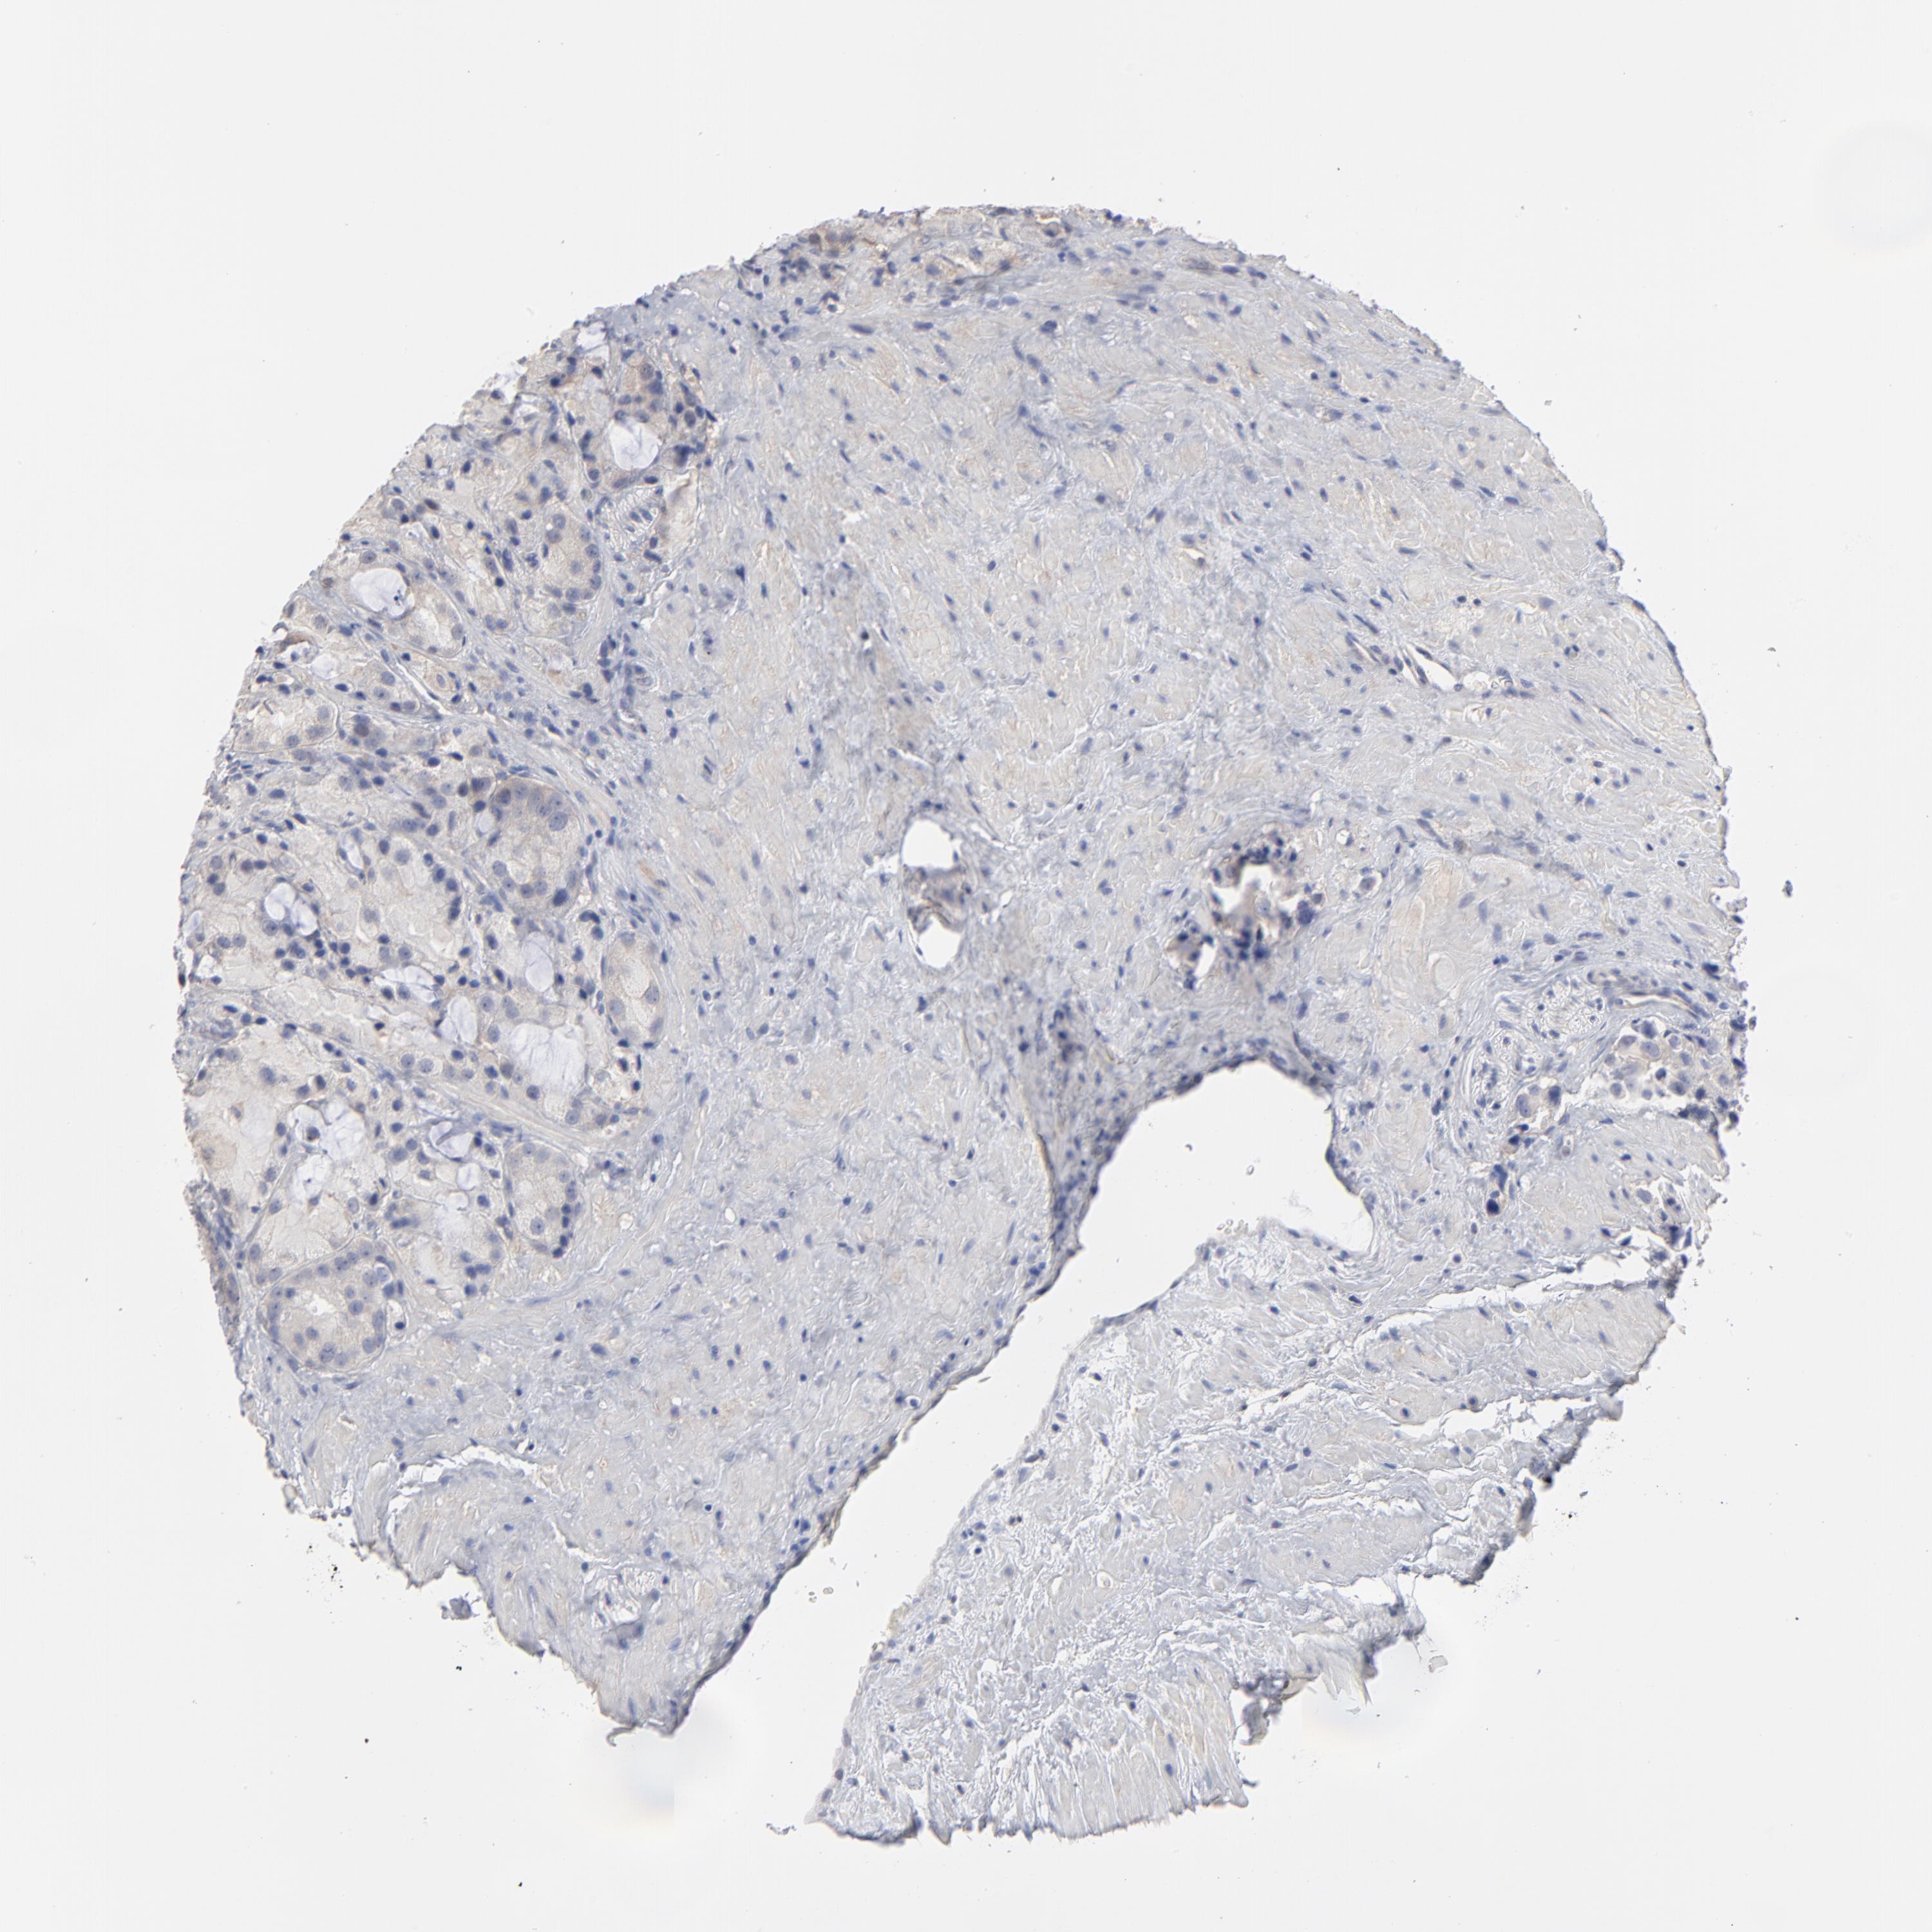

PROSTATE CANCER - Protein expressioni

A mouse-over function shows sample information and annotation data. Click on an image to view it in a full screen mode. Samples can be filtered based on level of antibody staining by selecting one or several of the following categories: high, medium, low and not detected. The assay and annotation is described here.

Note that samples used for immunohistochemistry by the Human Protein Atlas do not correspond to samples in the TCGA dataset.

Antibody stainingi

Antibody staining in the annotated cell types in the current human tissue is reported as not detected, low, medium, or high, based on conventional immunohistochemistry profiling in selected tissues. This score is based on the combination of the staining intensity and fraction of stained cells.

Each image is clickable and will lead to virtual microscopy that enables deeper exploration of all samples and also displays staining intensity scores, fraction scores and subcellular localization as well as patient and tissue information for each sample.

Antibody HPA003324

Staining

High

Medium

Low

Not detected

Intensity

Strong

Moderate

Weak

Negative

Quantity

>75%

75%-25%

<25%

None

Location

Nuclear

Cytoplasmic/membranous

Cytoplasmic/membranous,nuclear

Adenocarcinoma, Low grade

Adenocarcinoma, Medium grade

Adenocarcinoma, High grade